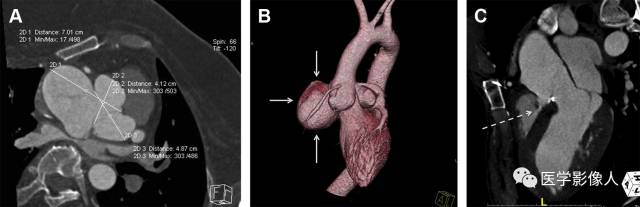

升主动脉瘤 医学百科网 | YxBaike.Com

主动脉环扩张 医学百科网 | YxBaike.Com

主动脉窦瘤 医学百科网 | YxBaike.Com